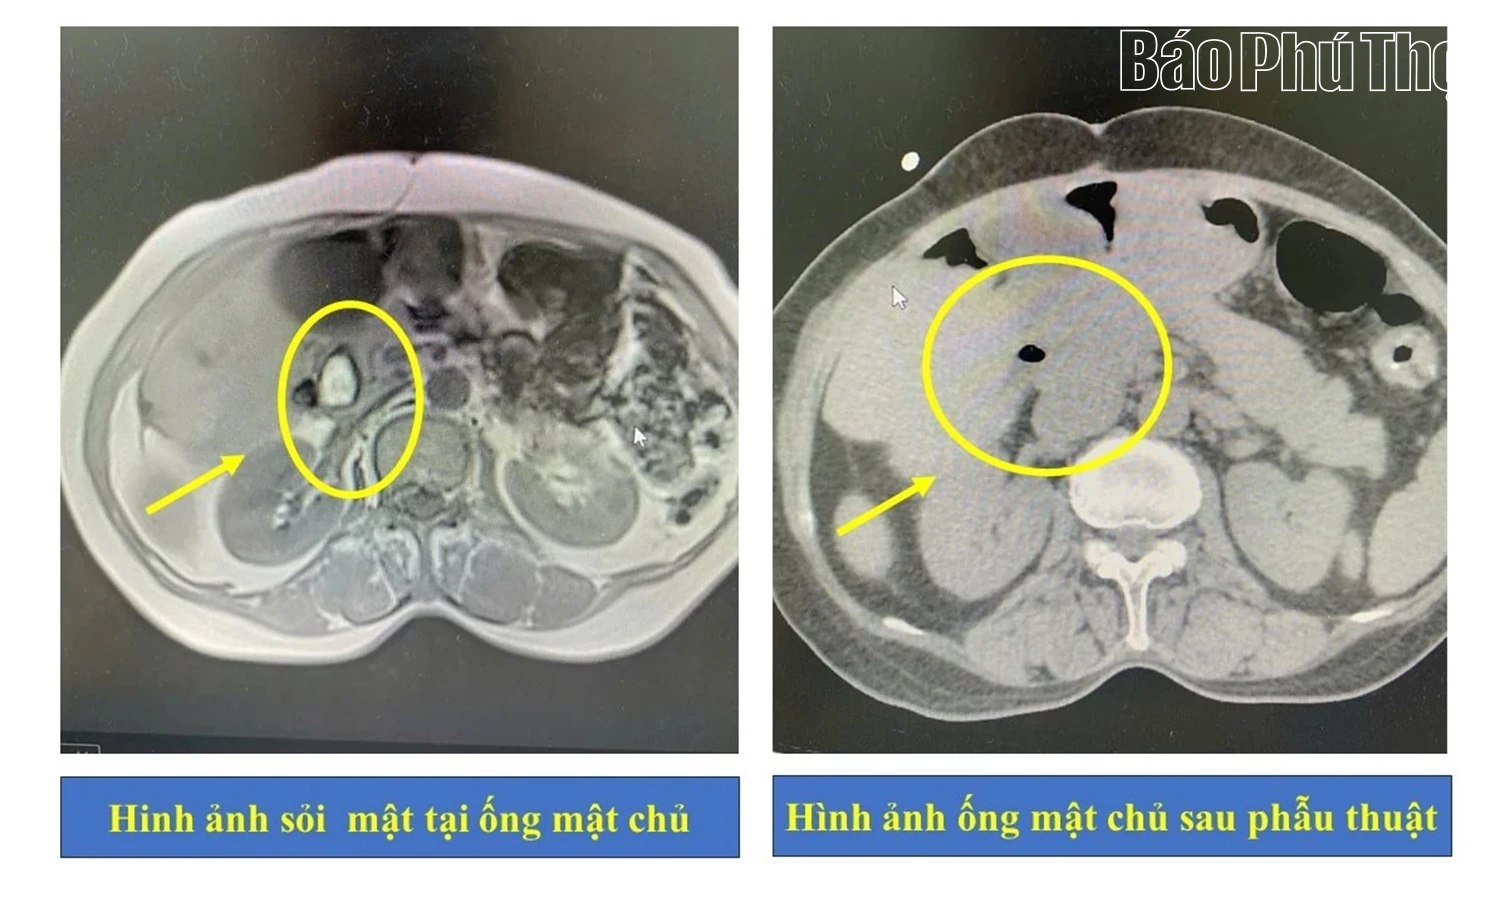

Hình ảnh ống mật chủ của người bệnh trước và sau phẫu thuật.

Người bệnh nhập viện tại Khoa Nội Hô hấp – Tiêu hóa trong tình trạng đau tăng dần vùng thượng vị và hạ sườn bên phải, kèm theo vàng da tăng dần, gây mệt mỏi và ảnh hưởng đến ăn uống, sinh hoạt. Sau khi thực hiện các cận lâm sàng cần thiết, kết quả cho thấy người bệnh bị nhiễm trùng đường mật, tắc mật do sỏi tại ống mật chủ.